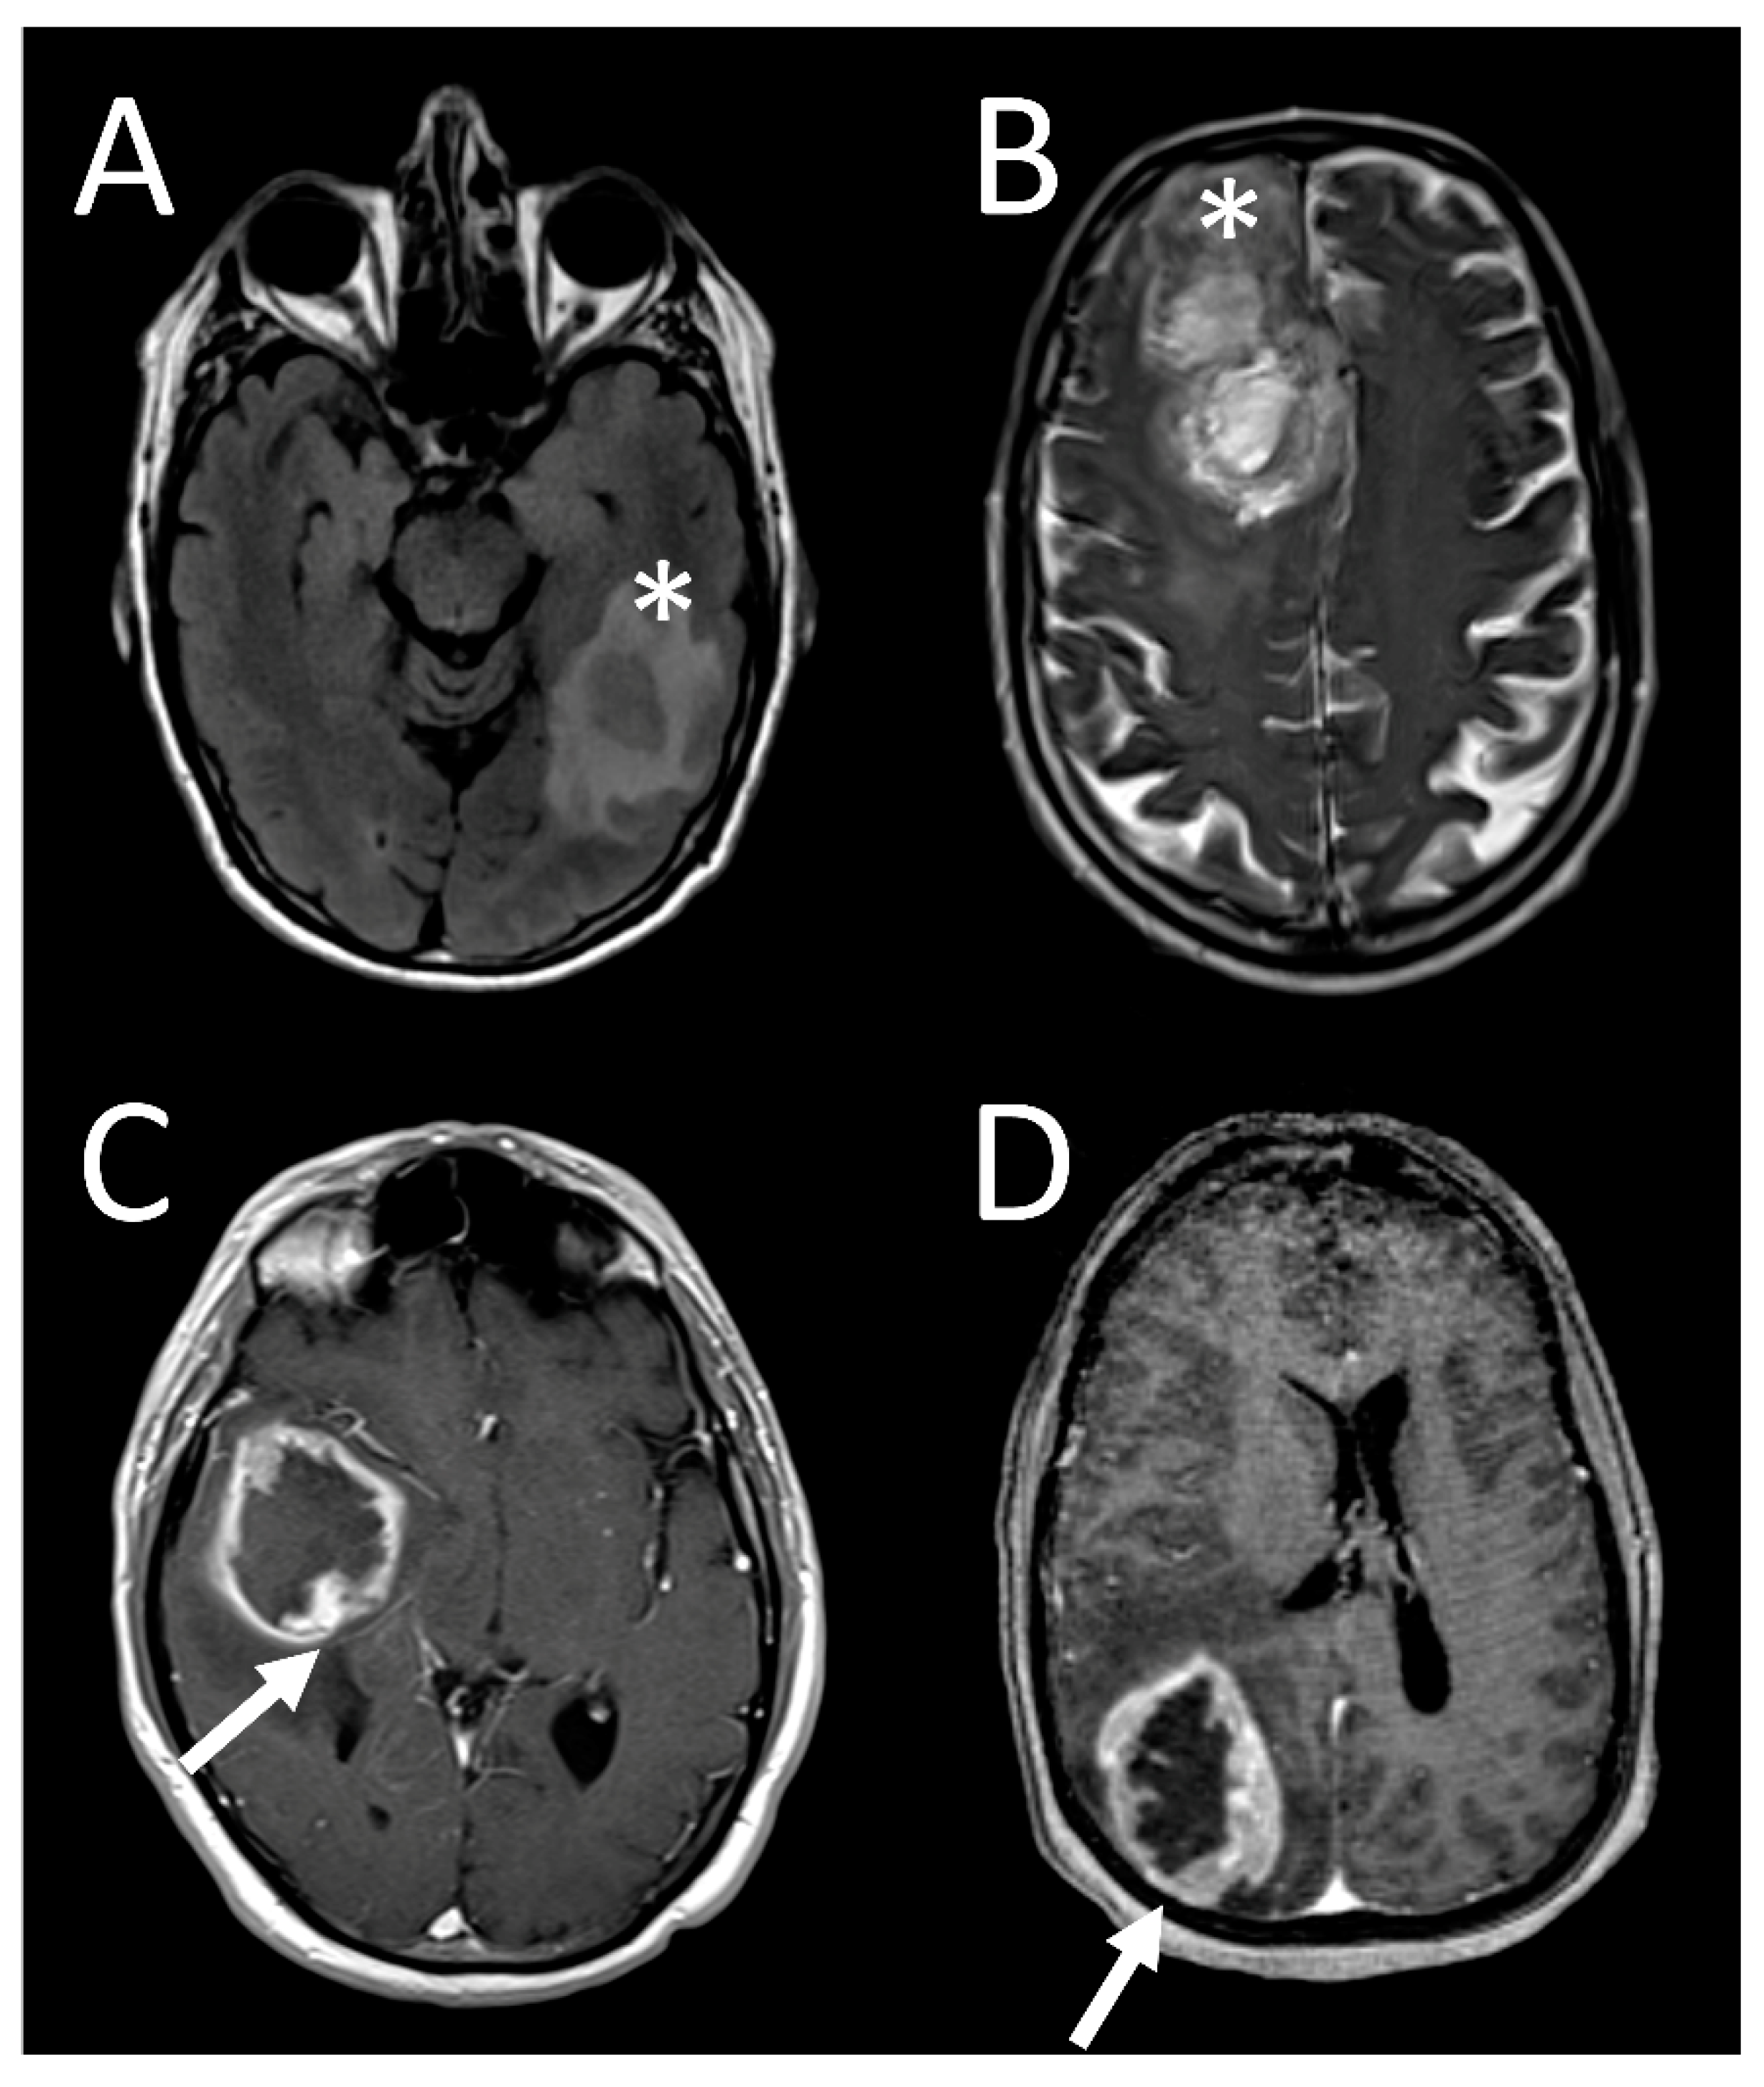

3.4. Tumor Characteristics